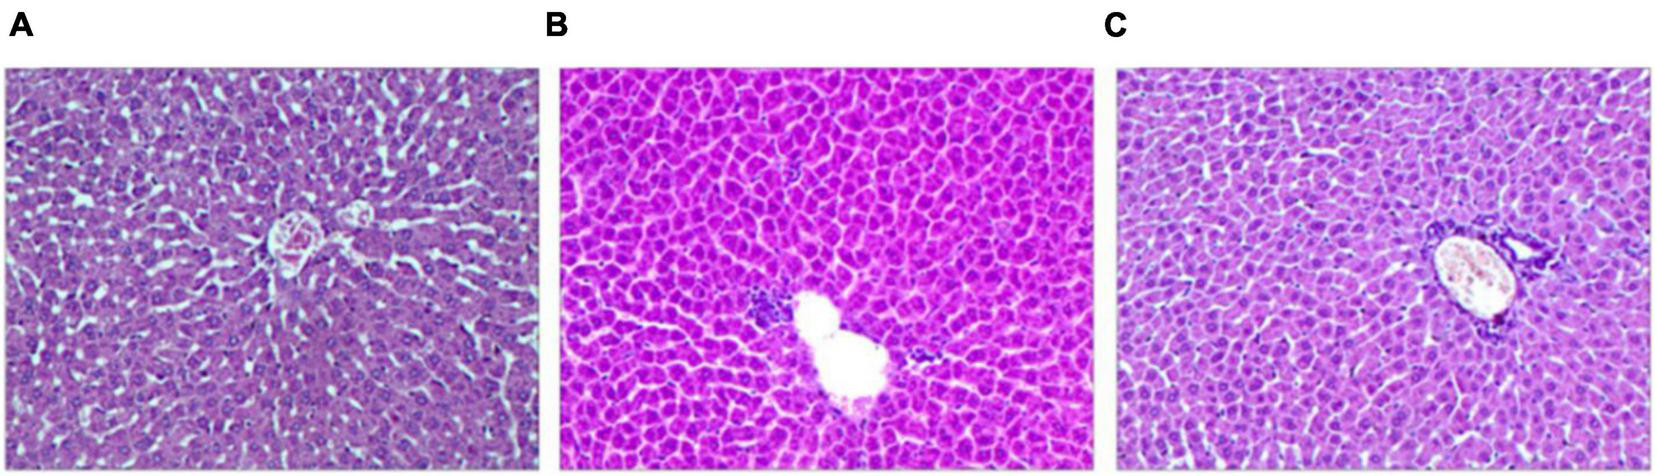

Comparison of Pathological Changes

The results show significantly pathological changes in the liver among the groups. The liver lobules of group P were integrity and clarity, the liver cells were arranged neatly (Figure 4A). Compared with group P, the rats in group H1 and group H2 revealed the liver injury and inflammation, had much inflammatory cell infiltration and edema (Figures 4B,C).

Finally, this study analyzed the pathological changes of rat liver tissue and the expression of CYP3A4. After acute hypoxia, rat liver tissue has many inflammatory cell infiltration and edema, which may affect the metabolism of the drug (Wang et al., 2017). The analysis of CYP3A4 protein expression further indicated that acute hypoxia significantly down-regulated the protein expression of CYP3A4. The half-life of the substrate sildenafil is prolonged, and the average residence time in the body is prolonged, indicating that its metabolism is slowed down. Thus, down-regulation of CYP3A4 protein expression is closely related to the slowing down of sildenafil metabolism (De Denus et al., 2018).